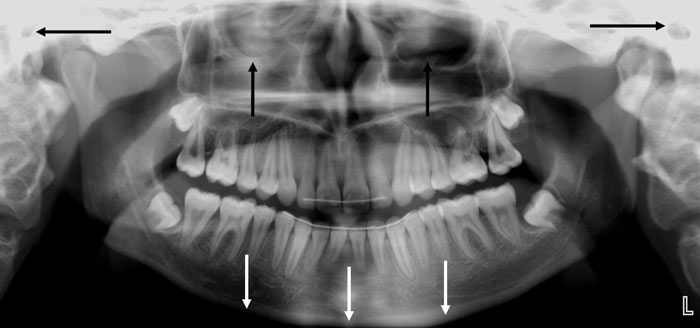

Panoramaradiografi er en røntgenteknik baseret på tomografi (snitfotografering), som resulterer i et billede af en patients underansigt. Et sådant billede benævnes et panoramabillede og skal i en standard version gengive patientens kæber i deres helhed. I praksis betyder det gengivelse af alle anatomiske strukturer fra øre til øre i horisontal retning og fra hagespids til bunden af øjenhulerne i vertikal retning (Fig. 1).

Fig. 1. Standard panoramabillede (horisontale pile markerer øreåbningerne, vertikale hvide pile markerer underkæbens nedre begrænsning og vertikale sorte pile markerer bunden af øjenhulerne).